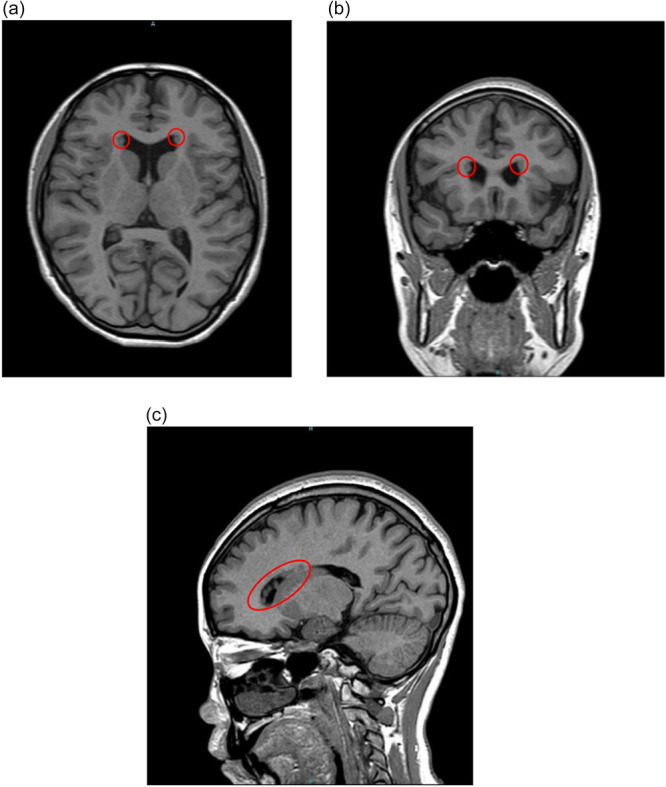

背景:22q11.2缺失综合征与精神分裂症、癫痫发作相关,并常出现抗精神病药物不耐受。脑室周围结节性异位(PNH)是一种神经元迁移障碍,也可在22q11.2缺失综合征患者中观察到。然而,据我们所知,氯氮平在难治性精神分裂症和22q11.2缺失综合征及PNH合并症青少年患者中的应用尚未见报道。病例介绍:一位患有难治性精神分裂症的17岁女性被转介到我院。她表现为幻听,行为混乱,失眠。由于锥体外系症状,多种抗精神病药物、情绪稳定剂、苯二氮卓类药物和改良电休克治疗无效或耐受性差。镇静下进行的脑磁共振成像(MRI)显示PNH。基因检测证实了22q11.2缺失综合征的诊断。开始时密切监测氯氮平,缓慢滴药后症状逐渐改善。大约6个月后出院,临床稳定15个月。结论:脑部核磁共振和基因检测——即使是在镇静状态下进行的——可能是难治性精神分裂症青少年患者有价值的诊断工具。此外,脑结构异常的存在并不妨碍氯氮平的疗效,氯氮平可能仍然是这种情况下可行和有效的治疗选择。

Case presentation: A 17-year-old female with treatment-resistant schizophrenia was referred to our hospital. She presented with auditory hallucinations, disorganized behavior, and insomnia. Multiple antipsychotics, mood stabilizers, benzodiazepines, and modified electroconvulsive therapy were either ineffective or poorly tolerated due to extrapyramidal symptoms. Brain magnetic resonance imaging (MRI) performed under sedation revealed PNH. Genetic testing confirmed a diagnosis of 22q11.2 deletion syndrome. Clozapine was initiated with close monitoring, and her symptoms gradually improved following a slow titration. She was discharged after approximately 6 months and has remained clinically stable for 15 months.